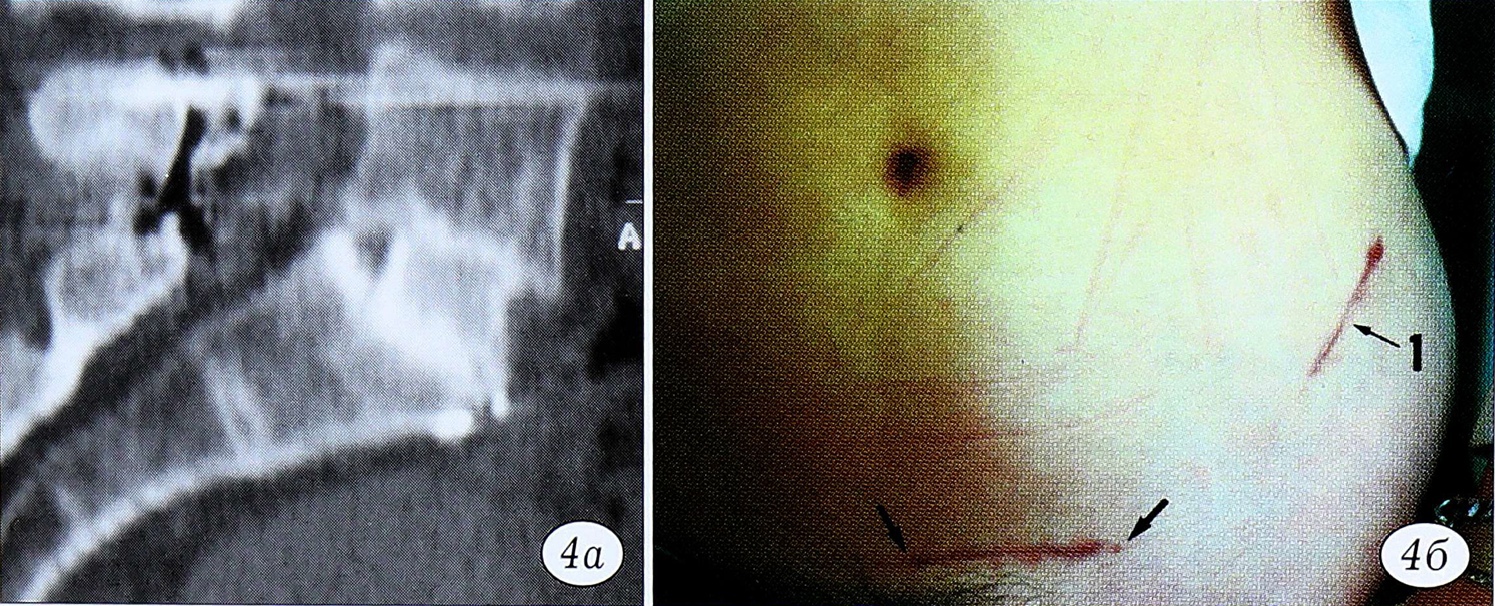

Доступ к L5-S1 (рис. 4) может быть как латеральным, так и медиальным, более классическим. Это зависит от выбранной стратегии подхода к межпозвонковому диску и трансплантату. В случае латеральных доступов (которые предпочтительнее у мужчин) необходимо контролировать восходящую поясничную и пояснично-подвздошные вены: их следует клипировать и коагулировать во избежание риска повреждения во время мобилизации общей подвздошной вены слева направо. Для изолированного подхода к уровню L5S1 прямой доступ более практичен, так как общая подвздошная артерия защищает вену. Однако в нашей практике эти случаи очень редки, гораздо чаще требуется одновременный доступ к L4-5 и L5-S1.

Рис. 4. Операция из переднего доступа к уровню L5~S1.a — сагиттальное изображение на сканограмме через 6 мес после операции; б — горизонтальный разрез кожи (обратить внимание на разрез кожи для взятия трансплантата).